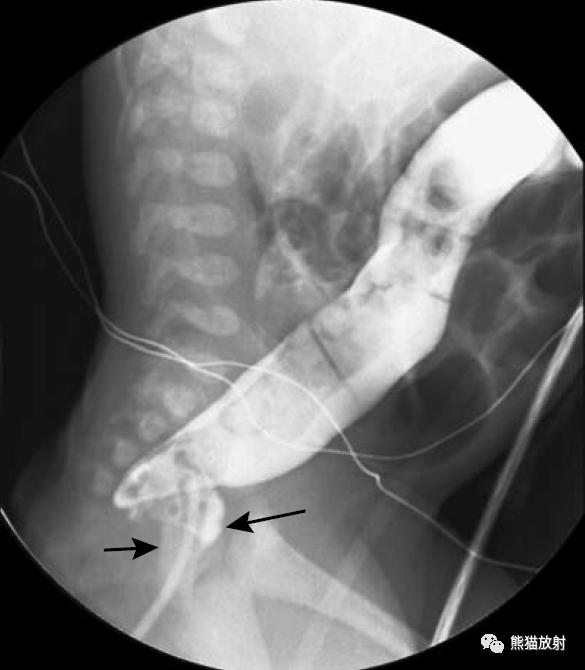

Hirschsprung病(先天性巨结肠)。钡灌肠可显示变窄的直肠(箭头)和近侧扩张的结肠。

(发病机制是远端肠管神经节细胞缺如或功能异常,使肠管处于痉挛狭窄状态,肠管通而不畅,近端肠管代偿性增大,壁增厚。)